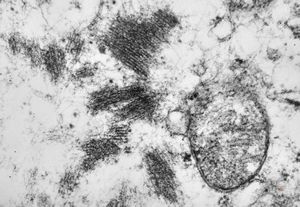

F,56y. | nemaline myopathy v.s.